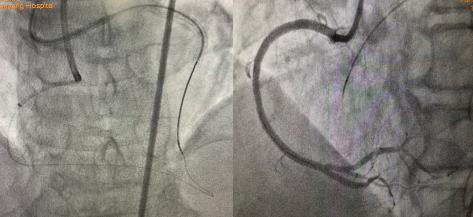

2021年9月26日秋雨綿綿,患者雙側(cè)指引導(dǎo)管造影示:如圖1。

圖1:右冠近段閉塞,前降支-穿膈支-后降支側(cè)枝循環(huán)形成CCI級(jí),J-CTO評(píng)分4分-高難度CTO病變。